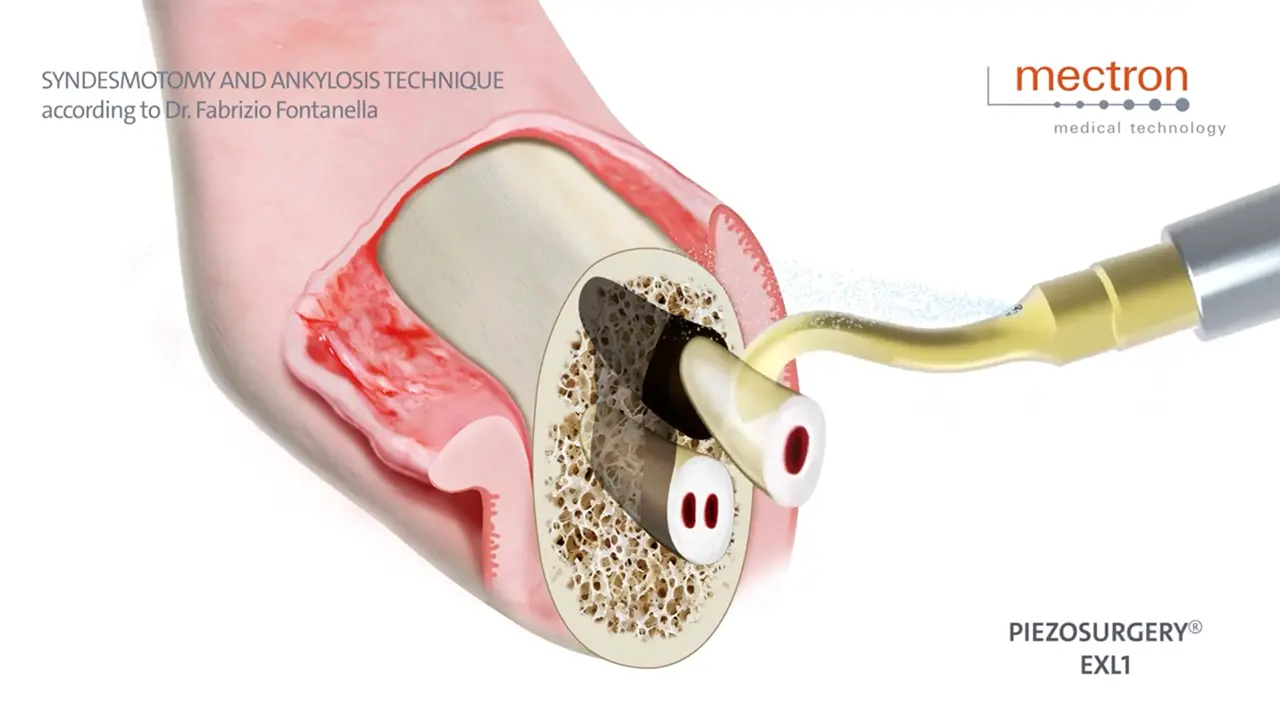

Syndesmotomy and ankylosis technique

Dr. Fabrizio Fontanella